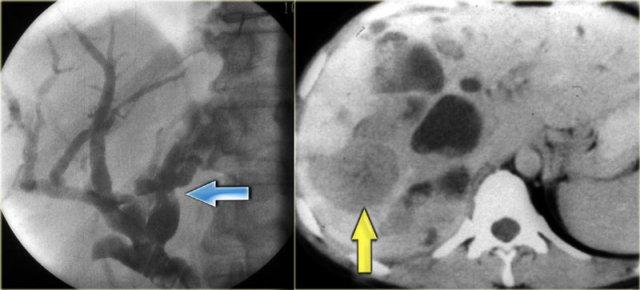

Hãy quan sát hình ảnh bên trái.

Sau đó tiếp tục đọc.

Các dấu hiệu bao gồm:

- Thận xốp tủy kèm hình thành sỏi (mũi tên đỏ)

- Giãn nhẹ ống mật (mũi tên xanh dương)

- Khối giảm tỷ trọng dạng tròn ở thùy gan phải

Khối ở thùy gan phải được xác định là áp xe.

Cần lưu ý rằng áp xe gan trong giai đoạn sớm có thể có hình ảnh khá đặc.

Trong chẩn đoán phân biệt, chúng ta cũng cần xem xét khả năng u tân sinh, vì bệnh nhân mắc bệnh Caroli có nguy cơ tăng cao phát triển ung thư biểu mô đường mật.

Cuối cùng, nếu có xơ hóa đáng kể và toàn bộ gan bị ảnh hưởng, những bệnh nhân này sẽ tiến triển thành xơ gan.

Bệnh nhân bên trái đã tiến triển suy gan nặng và được phẫu thuật cắt gan.

Lưu ý tình trạng giãn ống mật trong gan, lách to và giãn các tĩnh mạch bàng hệ.

Trên bệnh phẩm cắt bỏ có dấu hiệu chấm trung tâm (mũi tên xanh dương) và một ổ mủ nhỏ (mũi tên vàng).